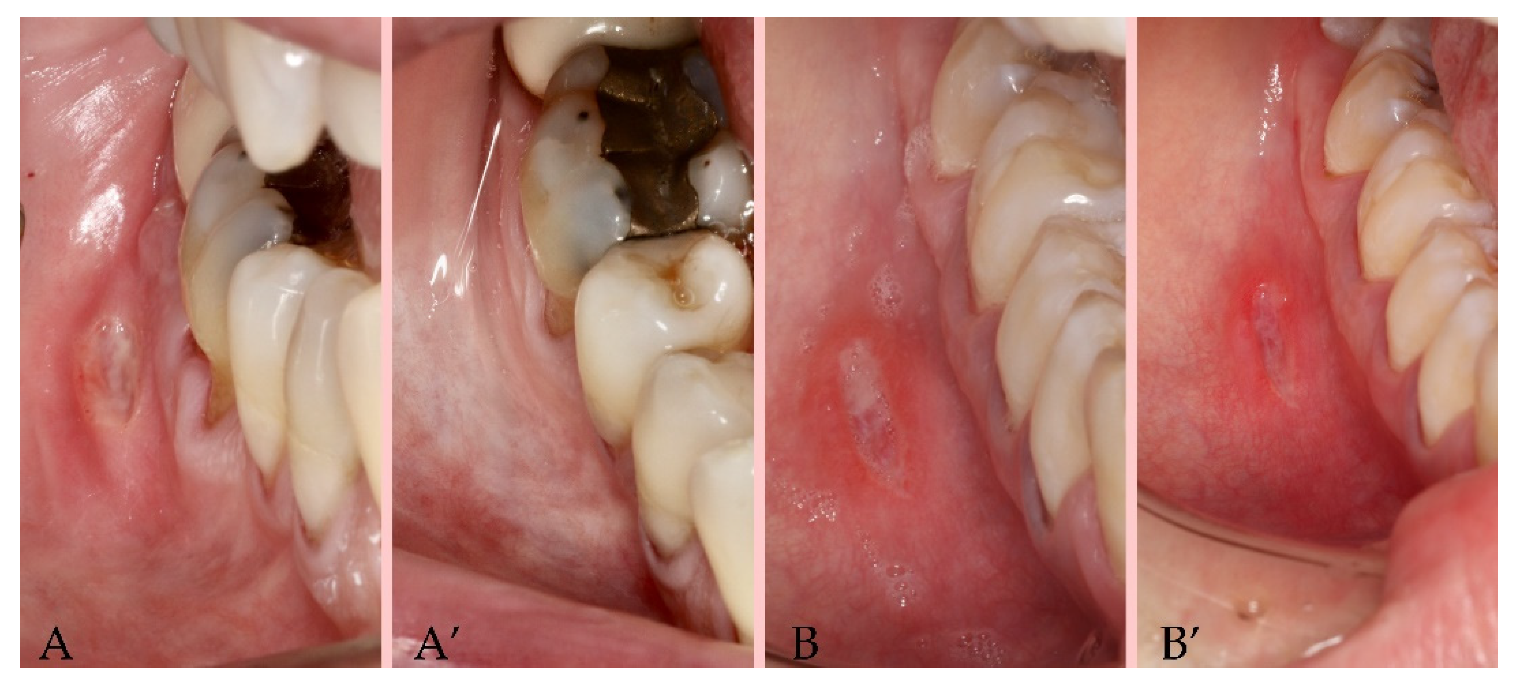

2.3. Procedures